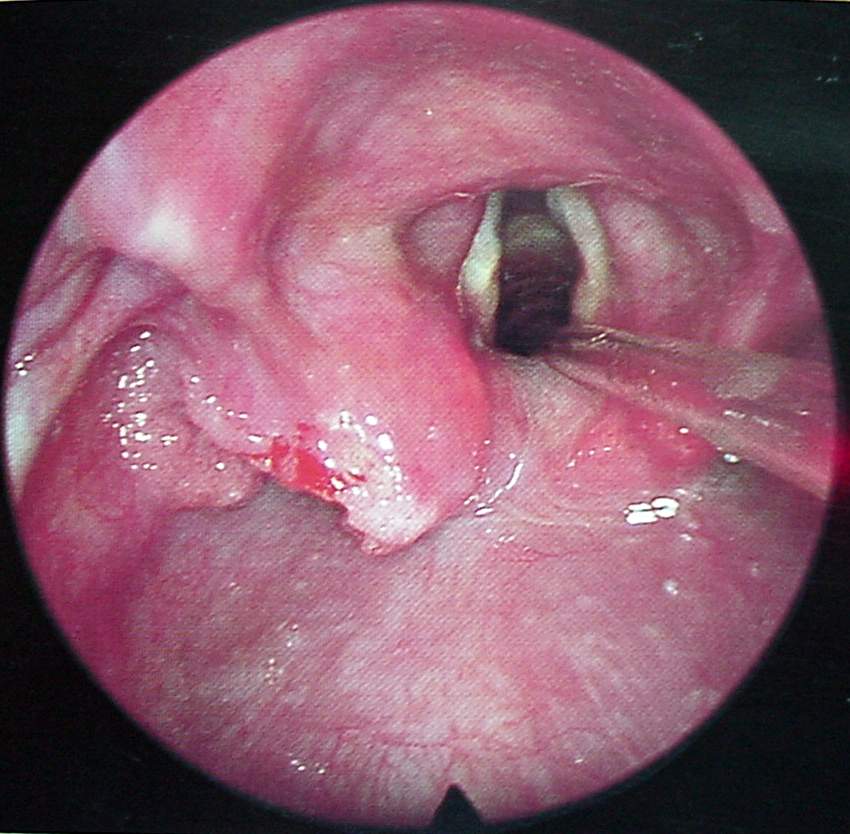

Pharynx and Esophagus Clinical Photos for Static Stations